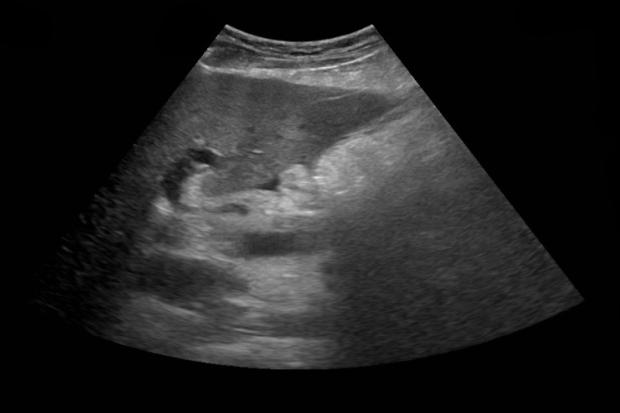

B超扇形图详解

B超扇形图一般代表肚皮,属于B超探头的横切面成像,宫颈口在B超成像的下方。

孕期进行B超并带有扇形图,能够直接的了解胎儿在孕妇腹中的情况,医生可直接观察胎儿的发育情况等好处。如果是宫内孕,可判断胚胎是否存活。

女性在怀孕期间,进行B超检查,可明确妊娠是否正常,并且可了解胎儿在子宫内的发育情况以及是否会出现异常现象等。在怀孕早期可通过B超发现女性属于宫内妊娠还是宫外孕,如果是宫内孕,可判断胚胎是否存活。在孕13周时,进行B超检查胎儿颈部的厚度,可直接判断胎儿有无异常现象等作用。